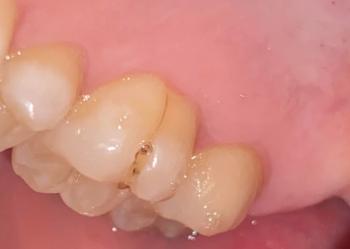

This image shows a patient wearing orthodontic braces with a large, painful ulcer on the inner lower lip. The sore has a yellowish center with surrounding redness and swelling, consistent with traumatic oral ulceration caused by repeated friction from brackets or archwire.

Single, well-defined ulcer on inner lower lip

Yellow or pale necrotic center

Red, inflamed surrounding tissue

Swelling of the lower lip

Brackets and wire in direct contact with affected area

Findings are suggestive of a traumatic mouth ulcer

Likely caused by continuous rubbing of braces during speaking and chewing

Orthodontic appliance–induced oral ulcer

Traumatic mucosal injury with secondary inflammation